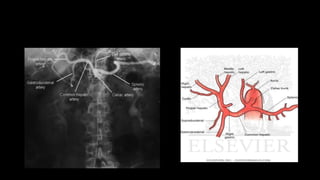

HEPATIC ARTERY

• At the liver hilum, before entering the

parenchyma, the hepatic artery bifurcates

into the right and left hepatic branches.

• The right hepatic artery (RHA) is larger, gives

off a cystic branch for the gallbladder and

bifurcates into anterior and posterior

branches just before entering the

parenchyma.

• The left branch divides into three vessels for

the anterior, posterior and caudate parts of

the left lobe.

• Hepatic arteries then give off segmental and

subsegmental arteries that run and branch

in the portal spaces.